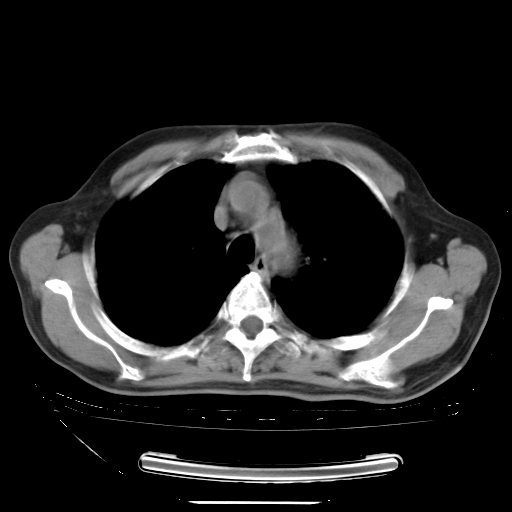

胸腹部CT,诊断意见:左上肺叶钙化灶、左侧胸膜局限性增厚并钙化、胆囊炎。描述部分肺组织呈磨玻璃样改变。

今天复查肺部CT,发现双肺广泛磨玻璃样改变。所以我把3月19日和5月9日相隔50天的肺部CT上传。请大家会诊。

2009年3月19日肺部CT片。

大致读了系列胸部CT:纵隔窗无明显异常,肺窗:从4、27至今:主要是双肺中下野外带可见毛玻璃样改变,目前处于急性肺泡炎阶段,至于原因考虑1、结替组织或胶原血管性疾病所致?2、恶性疾病如恶组在肺部所致的表现或细支气管肺泡癌?3、药物或其它原因如肺蛋白沉着症所致肺泡炎目前不太可能?总之,明天就去请我院的呼吸科、感染科、血液科和临免专家会诊哈。